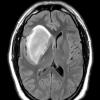

NEOPLASMS (GLIAL)

Astrocytoma, IDH-mutant, WHO Grade 2 (4)